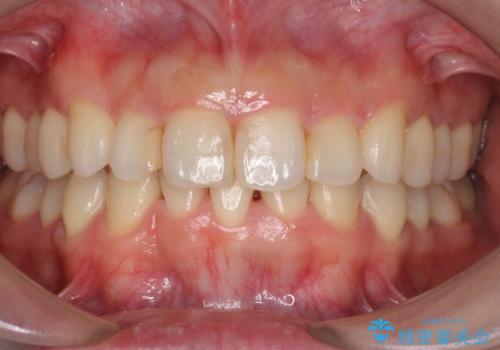

矯正歯科治療 → 叢生(でこぼこ・八重歯)

再矯正、後戻りを治したい、マウスピース矯正

途中で終わってしまったワイヤー治療もインビザラインで

上下の真ん中を合わせて横顔シルエットも改善

前歯のクロスバイトと抜歯が必要な奥歯の虫歯 インビザラインとインプラント治療

抜歯矯正の後戻りが気になる インビザライン・ライトによる矯正治療

インビザラインを用いた非抜歯矯正

インビザラインチェンジで成功 インビザラインで八重歯の抜歯矯正

前歯が気になる 大人のマウスピース矯正 矮小歯を整える

出っ歯 下の歯のガタガタ 下の前歯のみ1本抜歯 マウスピースで1年